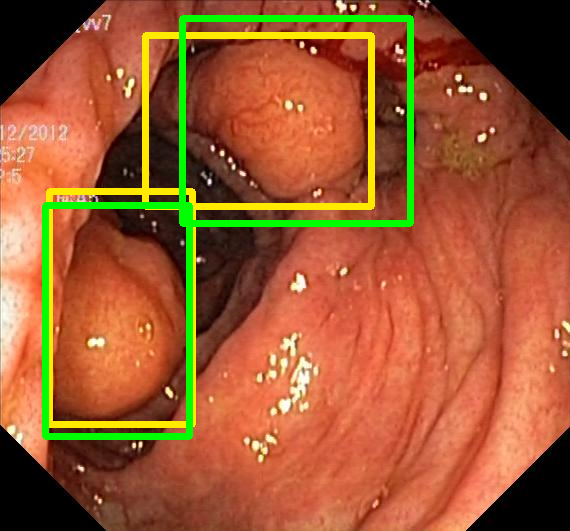

We evaluate the resulting object detection models using the test data, which is pre-processed in the same manner as the validation data, with AP@[.5:.95] (AP for conciseness), AP@.5 (AP50), and AP@.75 (AP75) computed for predicted bounded boxes with a confidence score \geq0.05. For all metrics, a higher value indicates better performance. The results are presented in Table VI, and some examples for predicted bounding boxes with a confidence score \geq0.5 are shown in Fig. 1.

Figure 1: Targets (yellow bounding boxes) and predictions (green bounding boxes) for two randomly selected instances of the Kvasir-SEG test set. For conciseness, we denote ResNet50s with RN, ViT-Bs with VT, Hyperkvasir-unlabelled with HK, ImageNet-1k with IN, MoCo v3 with MC, Barlow Twins with BT, MAE with MA, supervised pretraining with SL, and no pretraining with NA-NA.